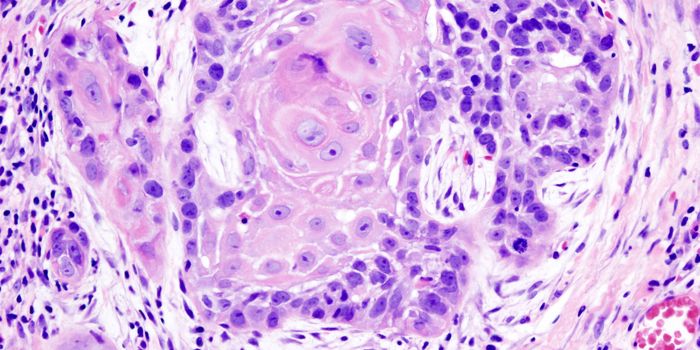

SEP 28, 2016ImmunologyA diet high in fat from specific sources is uniquely responsible for contributing to intestinal cancer through promoting ...